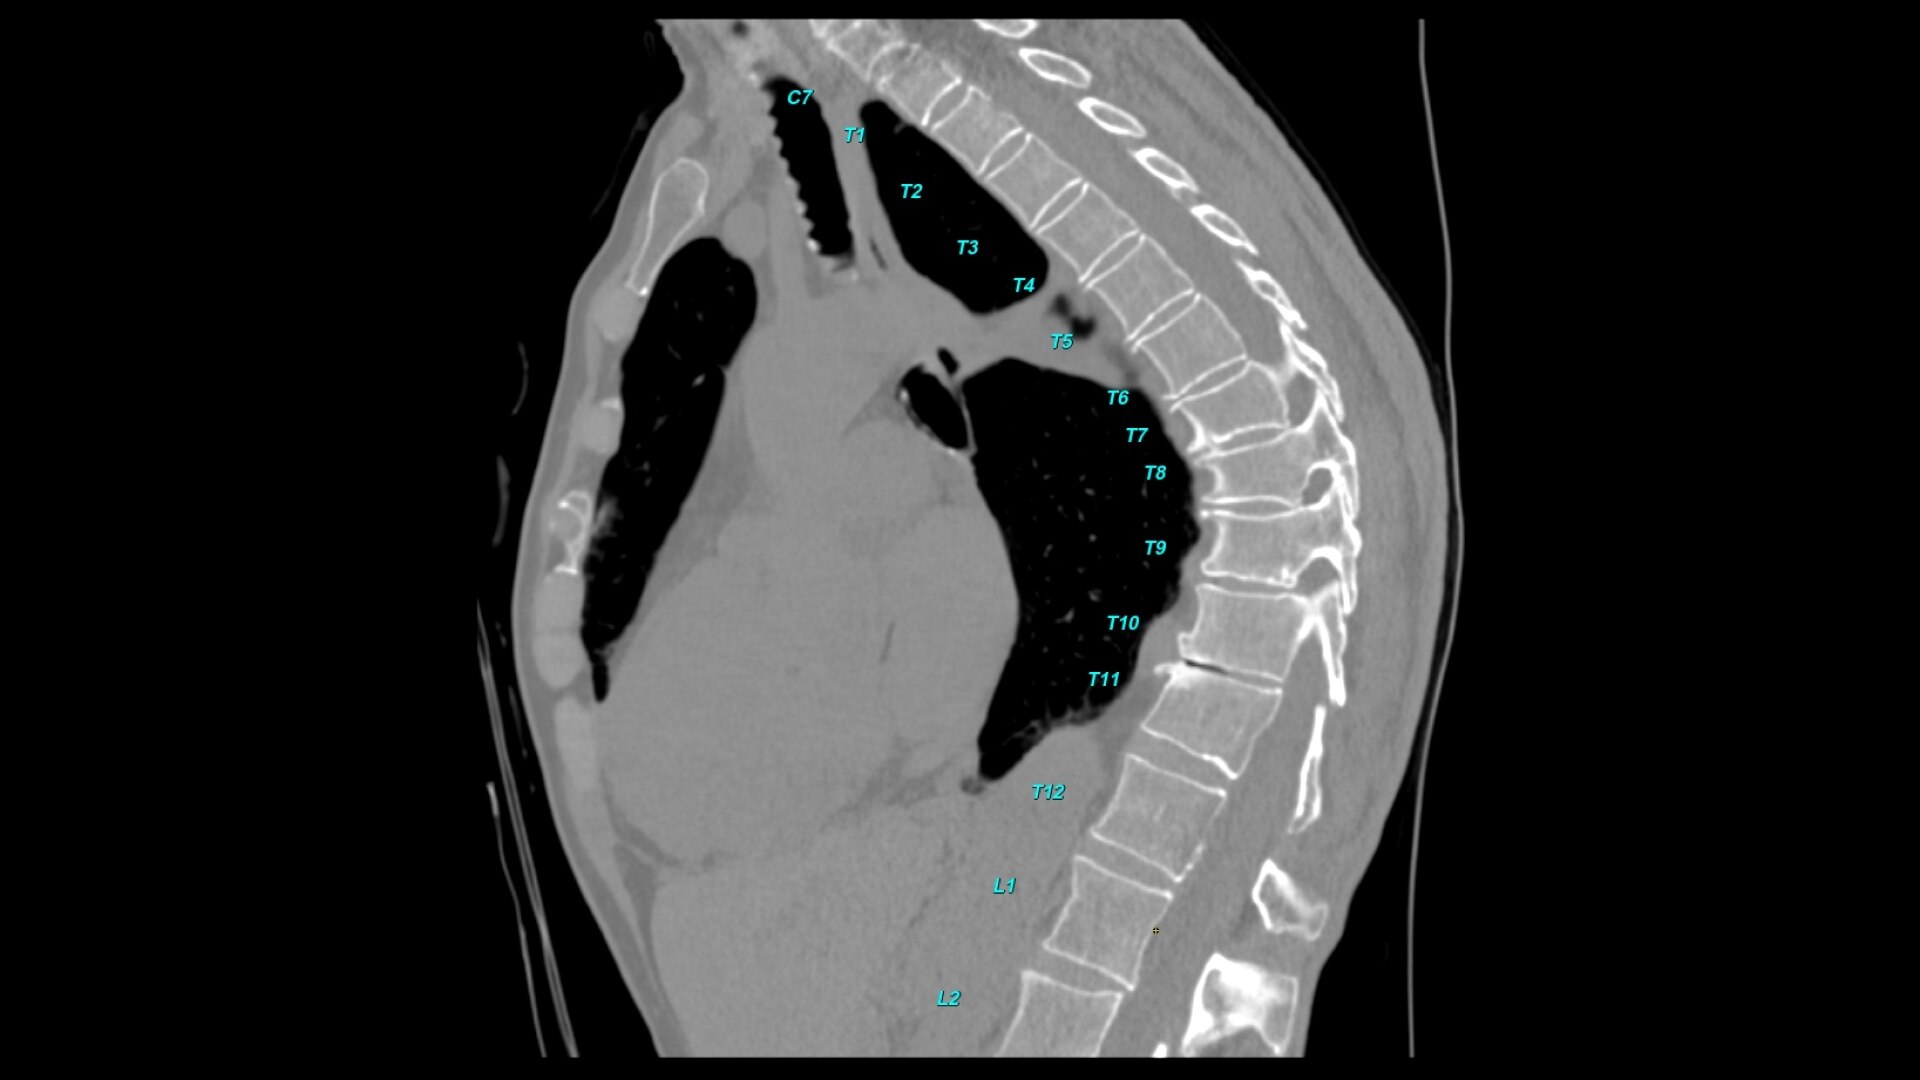

Bone VCAR

Spine assessment with deep-learning based CT application.

• Automated spine labeling

• Automated generation of a 3D trace to generate oblique and straightened reformat views

• Automated generation of oblique views perpendicular to vertebral bodies and disc spaces

• Accessible for any exam type: trauma, oncology, dedicated spine, general imaging